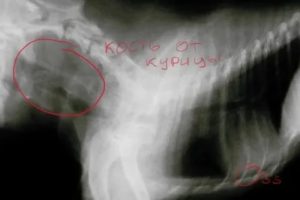

Иногда даже врач-ЛОР не всегда может визуально определить местонахождения косточки. Чтобы найти такую рыбью кость, необходимо сделать снимок, иногда даже нужно делать ФГДС пищевода.